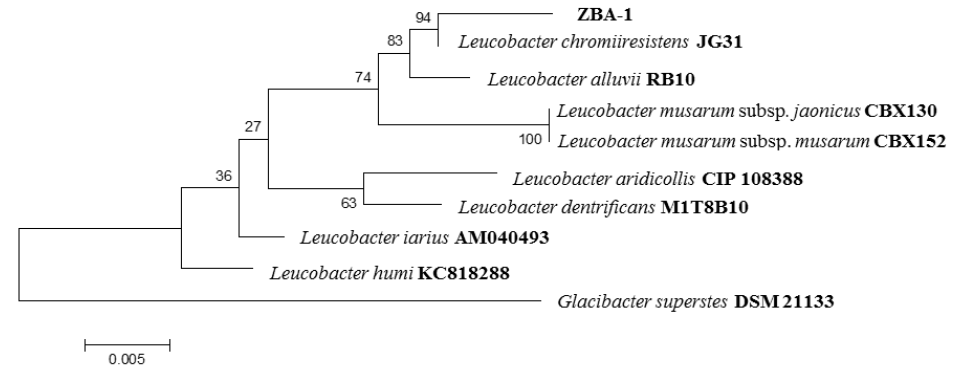

In the processing of sample by bacteriological techniques, growth of yellow-pigmented colonies was observed with presence of Gram positive bacilli. The isolated strain were identified by amplification, sequencing, and comparing of the 16S rRNA gene (Zaragoza et al., 2017). The results of molecular analysis showed that the strain it had a similarity of 99.4% with Leucobacter chromiiresistens (Table 1 and Figure 3).

Figure 3 Phylogenetic tree constructed by comparing the 16S rRNA gene sequence from the strain isolated and reference strains.

Table 1 Comparison of 16S rRNA gene sequences of the strains isolated with those deposited in GenBank, using BLAST and EzTaxon

| Strain | Size (Bp) | Similar species | Similarity Blast (%) | Similarity Eztaxon (%) |

|---|---|---|---|---|

| ZBA-1 | 1400 | Leucobacter chromiiresistens | 99 | 99.4 |

| Leucobacter alluvii | 98 | 98.7 | ||

| Leucobacter musarum subsp. japonicus | 98 | 98.0 | ||

| Leucobacter musarum subsp. musarum | 98 | 98.0 | ||

| Leucobacter humi | 97 | 97.7 | ||

| Leucobacter iarius | 97 | 97.4 |

Bp: base pair

The results of molecular analysis of bacteria determined that the strain it has a similarity of 99.4% with Leucobacter chromiiresistens, a Gram-positive, irregular rod-shaped, non- motile and yellow-pigmented bacterium, this species to date has no reports of infection in humans and animals (Sturm et al., 2011). In accordance with the literature, Escherichia coli, Klebsiella pneumoniae, Pseudomonas aeruginosa, Staphylococcus aureus, Streptococcus pneumoniae, Streptococcus pyogenes, and Bacteroides spp are most commonly associated with secondary infections in patients with cancer (Lopardo et al., 2014). In this regard, the Leucobacter genus is not common in secondary infections in patients with cancer, but there are reports of infection by this genus, mainly in patients with terminal cancer (Adderson et al., 2008). The injuries caused by the secondary infection by Leucobacter chromiiresistens were unidentified, because the necropsy was not authorized.